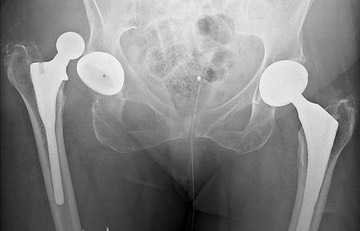

A revision hip replacement is an operation on a hip that has already had a hip replacement.  It is performed for a variety of reasons but frequently because the previous hip replacement has worn out.  The operation involves removing the failed components and inserting new ones. Often additional work is undertaken at the time of the operation to replace damaged or absent bone.

C0103496-Dislocated hip replacement, X-ray-SPL